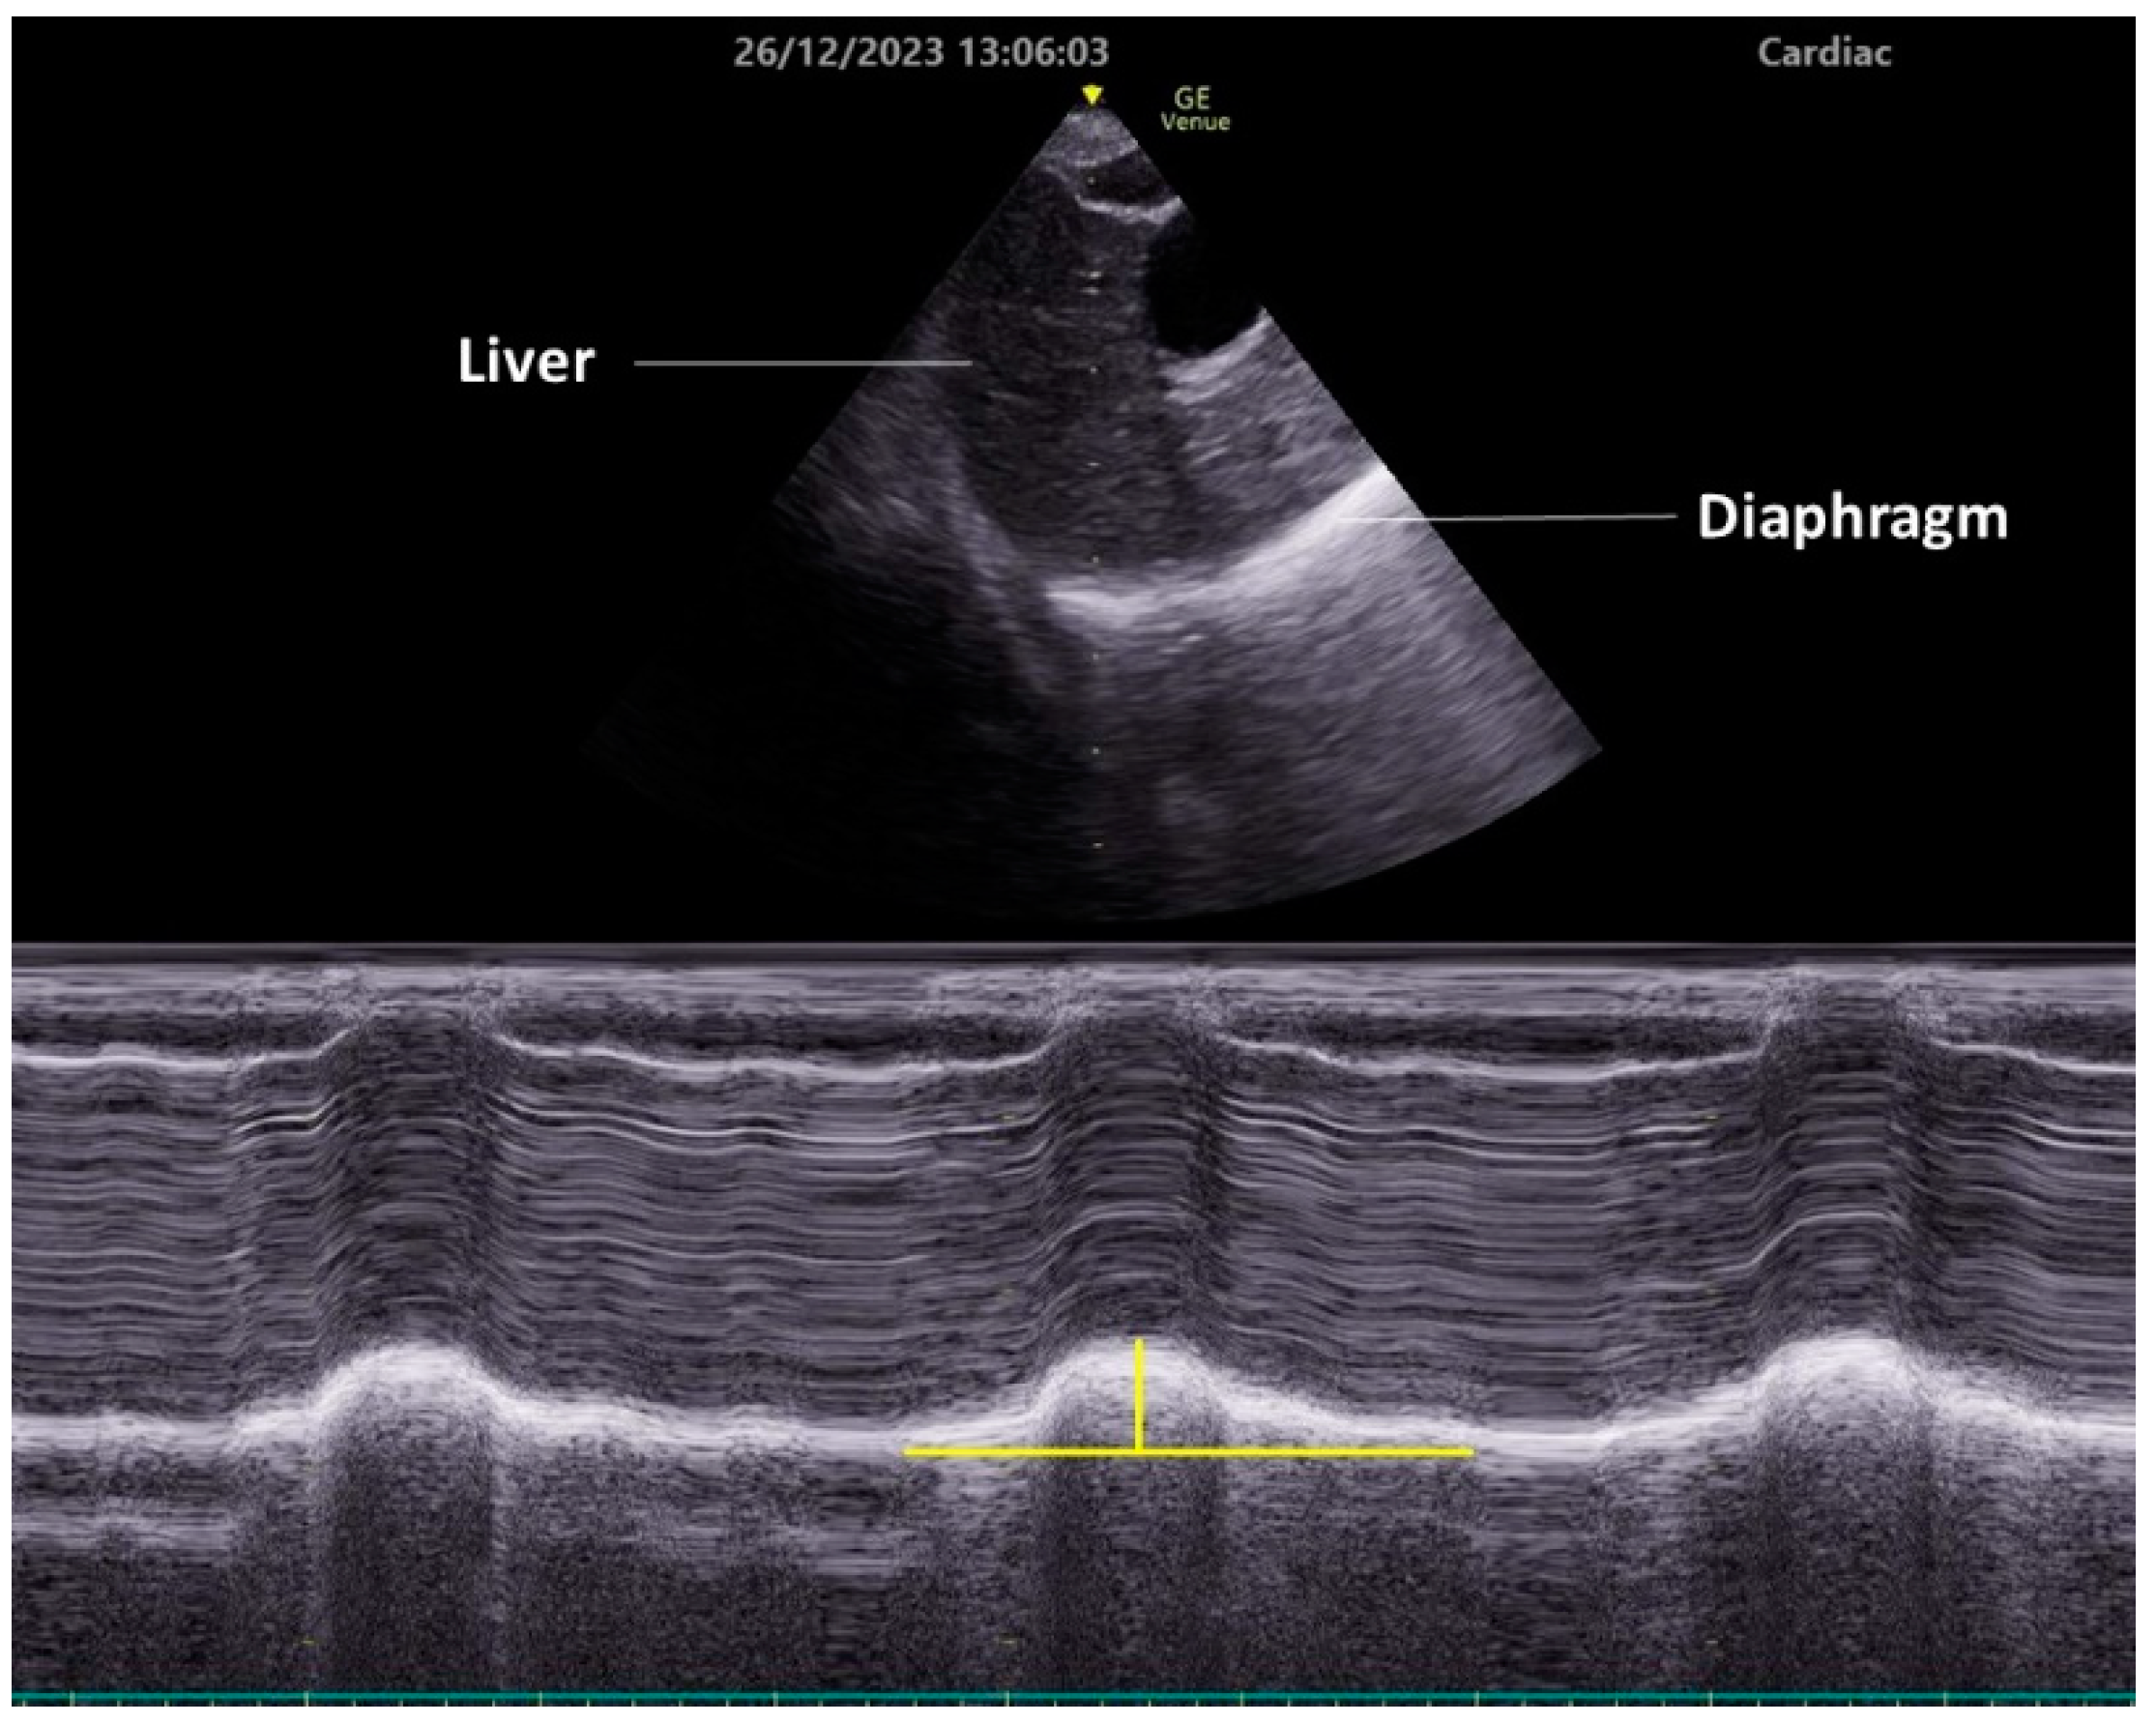

3.2. Subcostal Approach

4.2. Evaluation of Diaphragm Function

- Boussuges, A.; Gole, Y.; Blanc, P. Diaphragmatic motion studied by M-mode ultrasonography. Chest 2009, 135, 391–400. [Google Scholar] [CrossRef] [PubMed]

- Da Conceicao, D.; Perlas, A.; Giron Arango, L.; Wild, K.; Li, Q.; Huszti, E.; Chowdhury, J.; Chan, V. Validation of a novel point-of-care ultrasound method to assess diaphragmatic excursion. Reg. Anesth. Pain Med. 2023. [Google Scholar] [CrossRef]

- Dubé, B.P.; Dres, M.; Mayaux, J.; Demiri, S.; Similowski, T.; Demoule, A. Ultrasound evaluation of diaphragm function in mechanically ventilated patients: Comparison to phrenic stimulation and prognostic implications. Thorax 2017, 72, 811–818. [Google Scholar] [CrossRef] [PubMed]